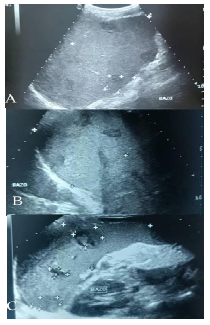

Acude a centro ambulatorio cercano donde solicitan ecografía abdominal con hallazgos de hepatomegalia por lo que refieren a nuestro centro, decidiendo hospitalización bajo tratamiento sintomático con diagnóstico de hepatitis aguda a descartar, se realiza nuevamente ecografía con experto que arroja hepatoesplenomegalia (Figura 2) y bazo midiendo longitudinalmente 13,1 cm con lesiones nodulares mixtas en su interior tipo microabscesos (Figura 3), discreta ascitis sin signos de hipertensión portal (Figura 4). Sin embargo, paciente persiste con ictericia, coluria y acolia, asociándose durante hospitalización epistaxis unilateral y melena en 2 oportunidades más somnolencia, planteándose descartar hepatitis autoinmune, siendo valorada por inmunología quien solicita los siguientes laboratorios: Anticuerpos anti-músculo liso (SMA), anticuerpos antinucleares (ANA) e Inmunoglobulina G (IgG) sérica total, todos resultando negativos. Posteriormente se reciben antígenos febriles (Widal) positivos para S. tiphy O 1/ 20 y S. tiphy H en títulos de 1/40, además de coprocultivo tomado por Instituto Nacional de Higiene Rafael Rangel de Caracas Venezuela positivo para S. typhi grupo H.

Figura 2 Ecografía abdominal Julio 2025. A. Hepatomegalia con parénquima homogéneo sin lesiones B. Lesiones esplénicas tipo microabscesos